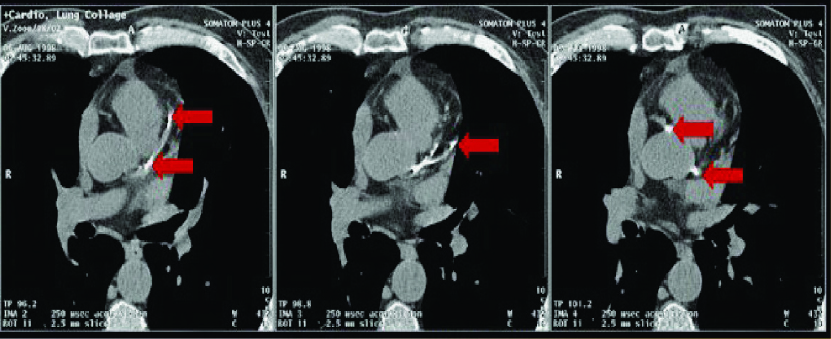

Coronary Artery Calcium Scoring is a non-invasive exam used to detect coronary heart disease (Atherosclerosis) or calcium build-up in the coronary arteries of the heart. The amount of calcium present is related to your risk for a heart attack.

Your calcium score can detect early signs of heart disease and your risk for a heart attack. It can detect build up of plaque in the arteries that supply blood to your heart.